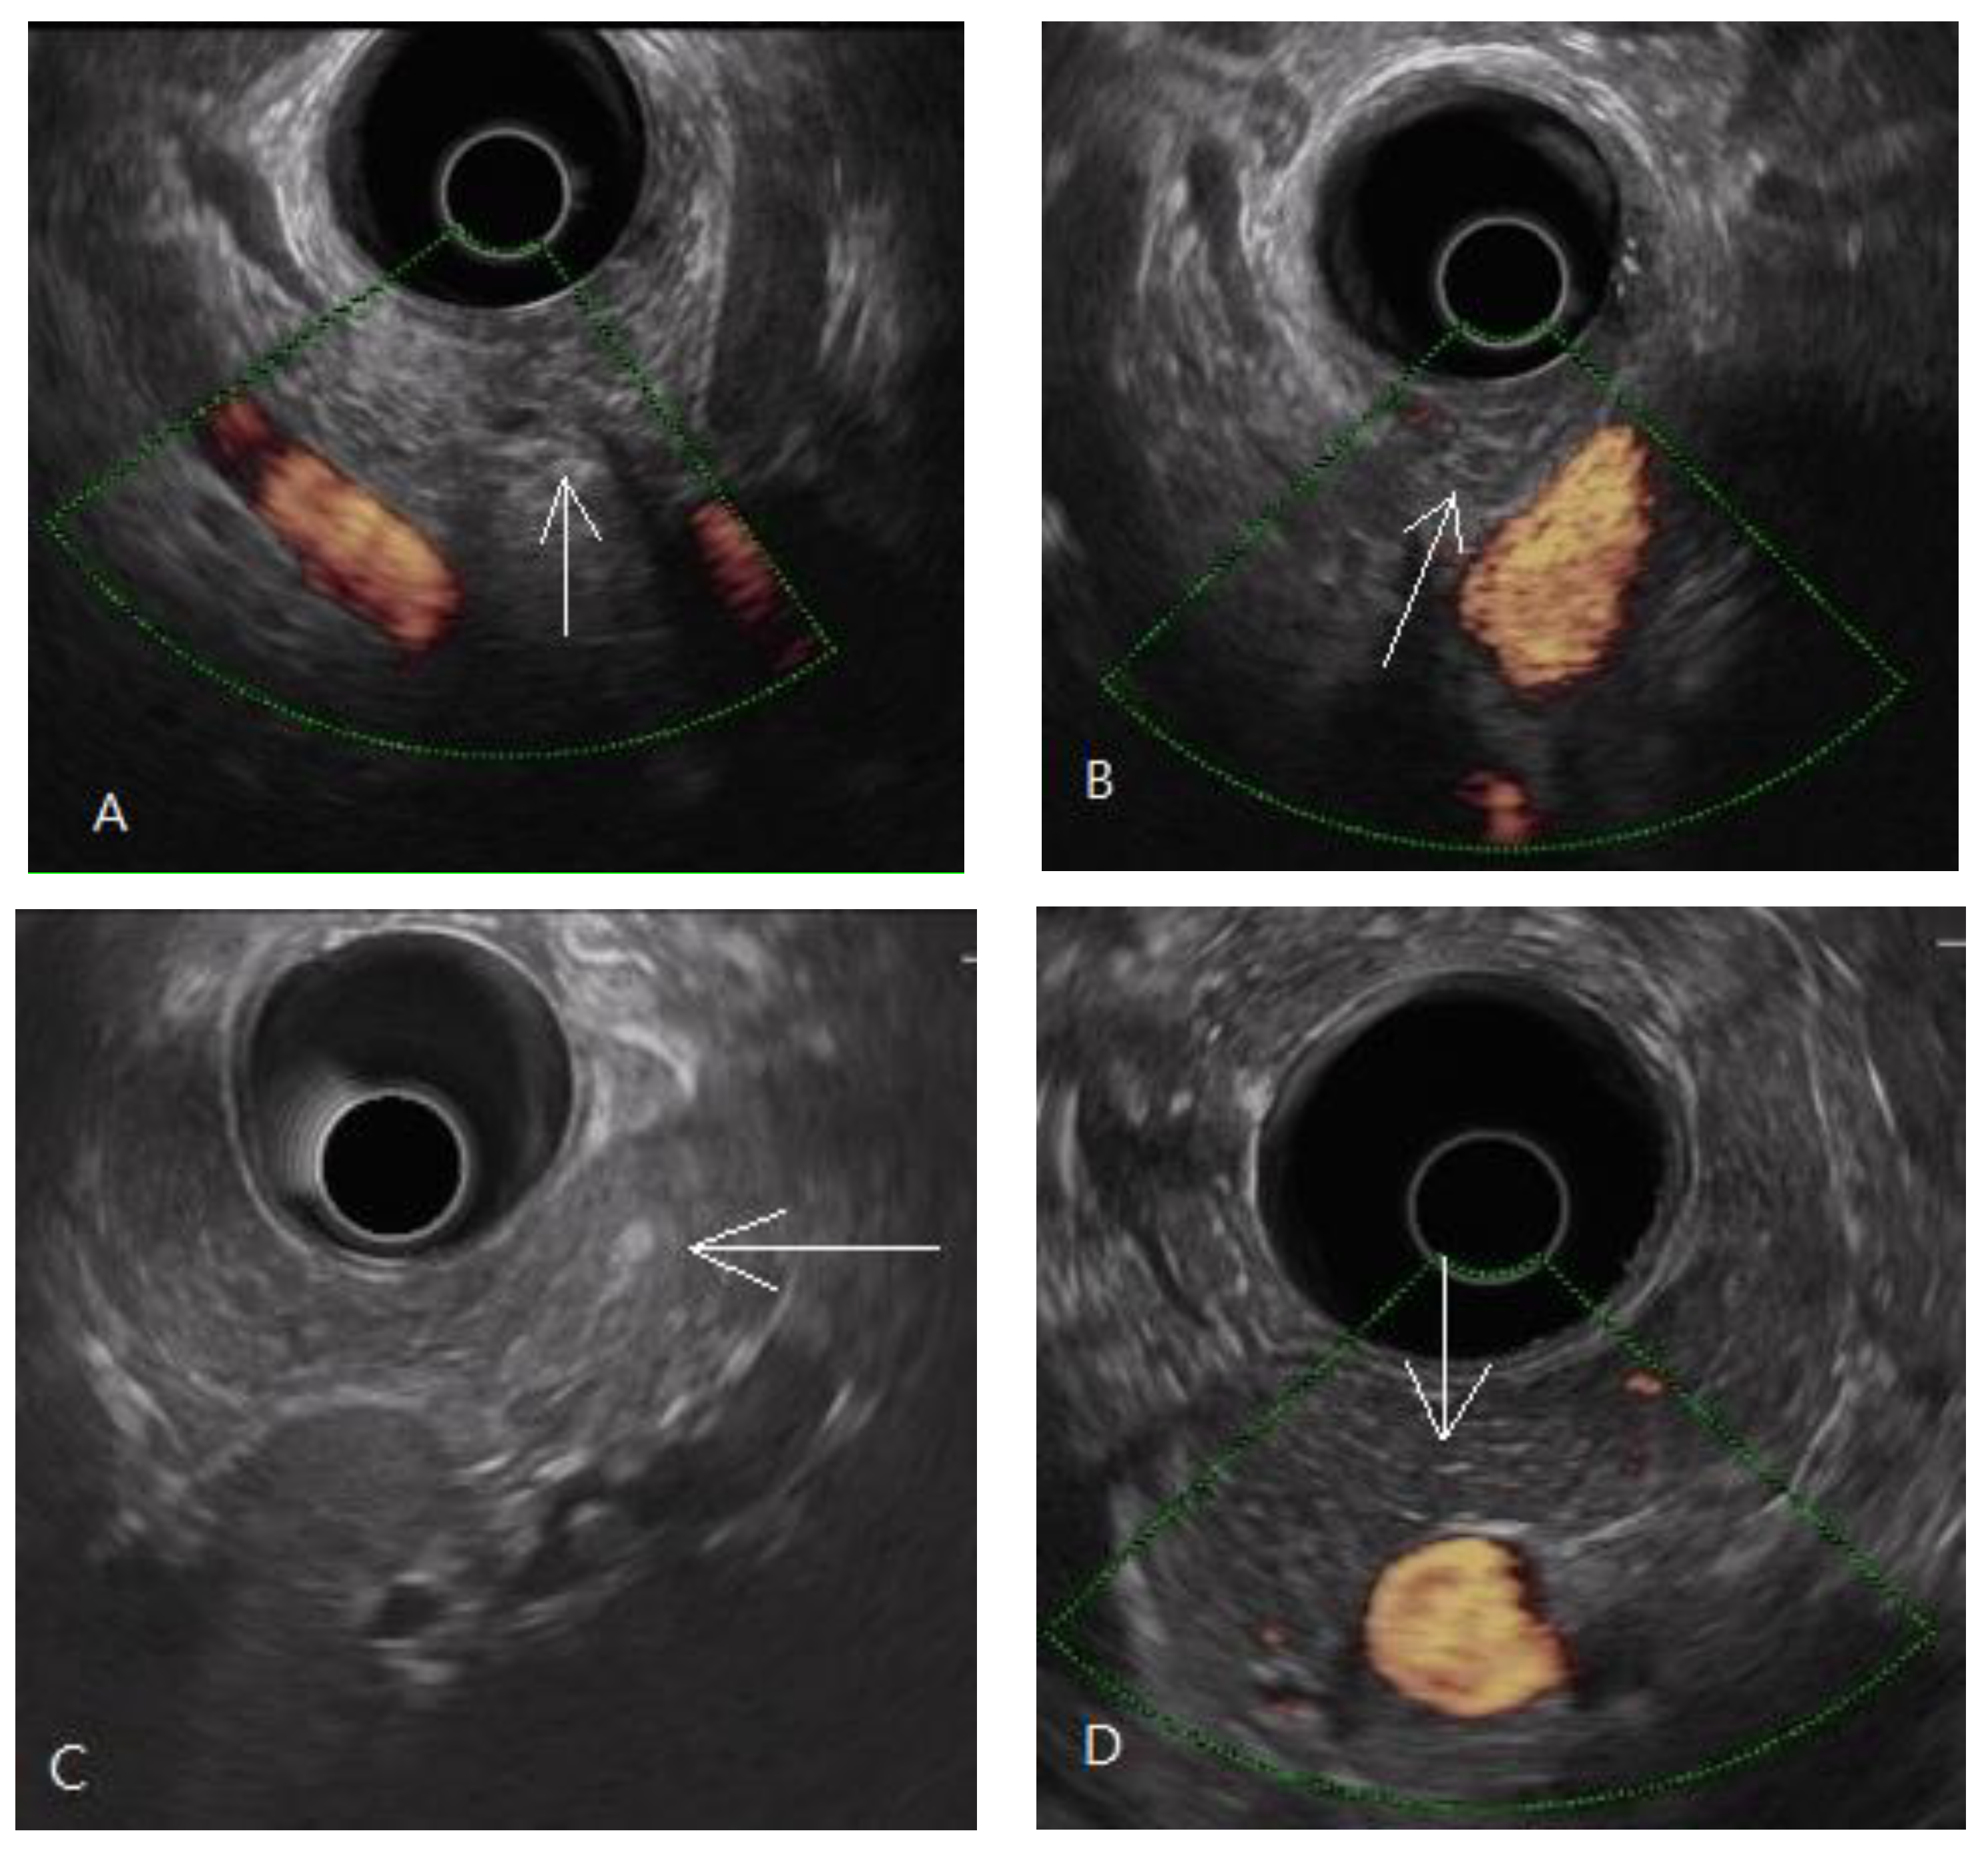

In this study on the dyspeptic population, early chronic pancreatitis was defined as pathologically equivalent to pancreatic fibrosis. Pancreatic fibrosis is a term for image diagnosis conventionally used in shear wave elastography, computed tomography, and magnetic resonance imaging [17,38]. Early chronic pancreatitis is a diagnostic term for the EUS procedure first introduced in the nomenclature by a review article published in 1995 [39]. A prospective study using EUS to diagnose alcoholic early chronic pancreatitis was published in 2002 [13]. In the past two decades, early chronic pancreatitis has mostly been diagnosed by EUS in studies [14,15,21,40,41,42,43,44,45]. By definition, early chronic pancreatitis is a syndrome requiring symptoms, risk factors, biomarkers, and image diagnosis, according to an international consensus [19]. The EUS criteria for diagnosing early chronic pancreatitis or chronic pancreatitis were proven to be histologically related to pancreatic fibrosis with approximately 80% accuracy [46,47]. The fibrotic change in the pancreas was focal occurrence [46]. It was evidenced in the distribution of the EUS diagnostic criteria for early chronic pancreatitis, as shown in Figure 2. There was also evidence of focal fibrosis in the pancreatic ARFI procedure, as shown in Figure 5.

Figure 5.

Three trans-abdomen sonographic images of the pancreas in the same patient. (A) Some hyperechoic foci in the pancreas; (B) if there are no hyperechoic foci in the region of interest, the pancreatic ARFI is 1.4 m/s; and (C) if there are hyperechoic foci in the region of interest, the pancreatic ARFI is higher (1.59 > 1.4 m/s).